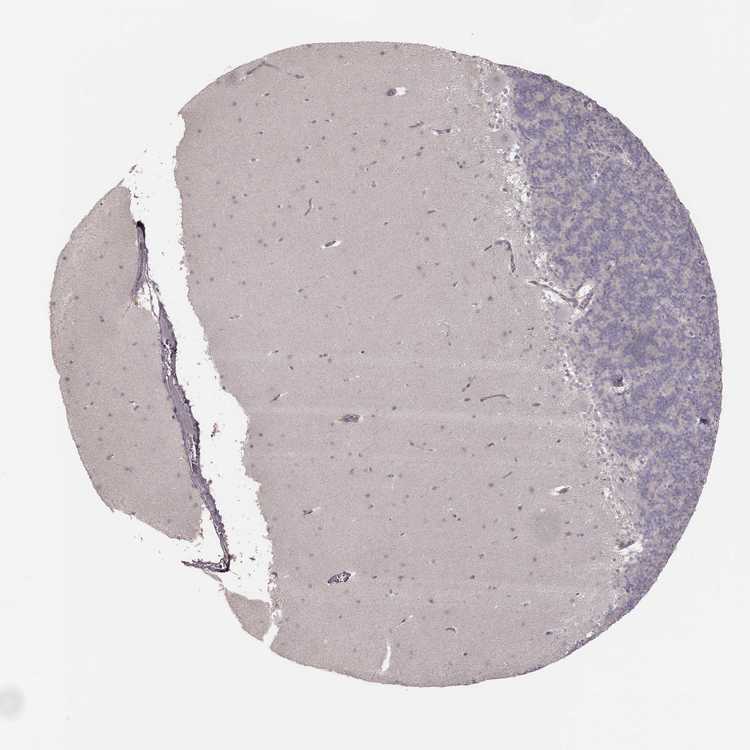

CEREBELLUM - Antibody stainingi

Antibody staining in the annotated cell types in the current human tissue is reported as not detected, low, medium, or high, based on conventional immunohistochemistry profiling in selected tissues. This score is based on the combination of the staining intensity and fraction of stained cells.

Each image is clickable and will lead to virtual microscopy that enables deeper exploration of all samples and also displays staining intensity scores, fraction scores and subcellular localization as well as patient and tissue information for each sample.

Antibody HPA029418

Purkinje cells Not detected

Cells in granular layer Not detected

Cells in molecular layer Not detected